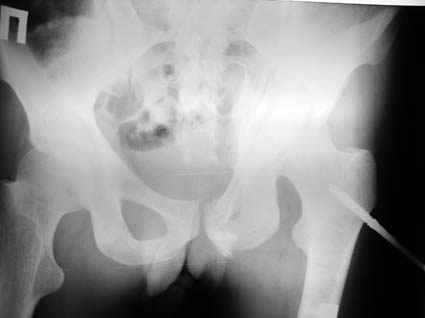

Все-таки надо бы начать не с КТ, а с обзорного снимка таза и косых проекций впадины.

Это обзорные и косые снимки

Привет, Леонид. Оскольчатый высокий двухколонный перелом в такие сроки трогать не надо, т.к. это про такие переломы сказано: "кто с ножом на Ж. пойдет тот в ней и останется...".